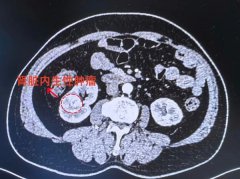

当一个不定时炸弹深埋于肾脏 是选择一刀切以绝后患 还是迎难而上为患者保肾? 近日,南通六院泌尿外科主任钱麟团队,成功为一名63岁的患者实施了高难...